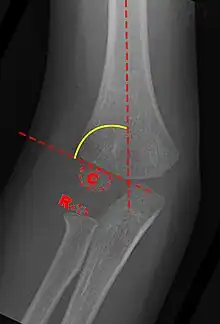

Carrying angle can be evaluated through AP view of the elbow by looking at the Baumann’s angle.[3] There are two definitions of Bowmann's angle:

The first definition of Baumann's angle is an angle between a line parallel to the longitudinal axis of the humeral shaft and a line drawn along the lateral epicondyle.

Another definition of Baumann's angle is also known as the humeral-capitellar angle. It is the angle between the line perpendicular to the long axis of the humerus and the growth plate of the lateral condyle. Reported normal values for Baumann's angle range between 9 and 26°.[7] An angle of more than 10° is regarded as acceptable.[7]